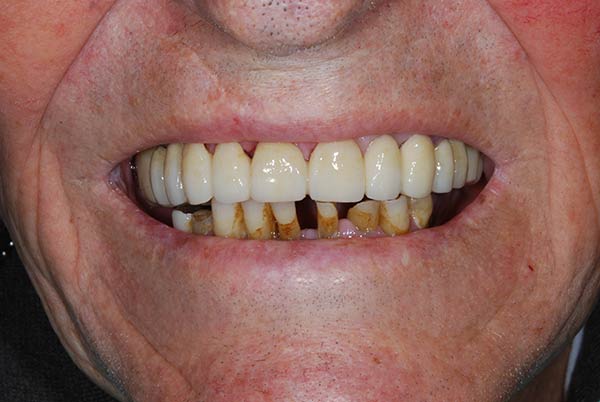

Con protesi fissa superiore e protesi fissa inferiore

I denti irrecuperabili dell'arcata superiore ed inferiore del paziente di anni 65 sono stati sostituiti da 10 impianti, cioè protesi radicolari endo-ossee che sostengono le protesi fisse superiore ed inferiore.